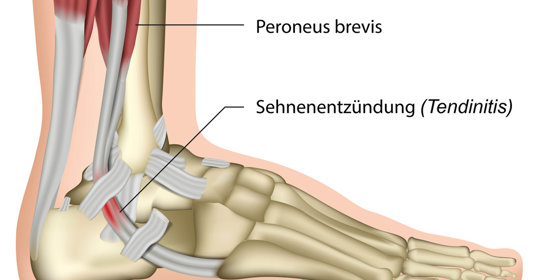

嬰兒腳內彎:原因、判斷及醫治